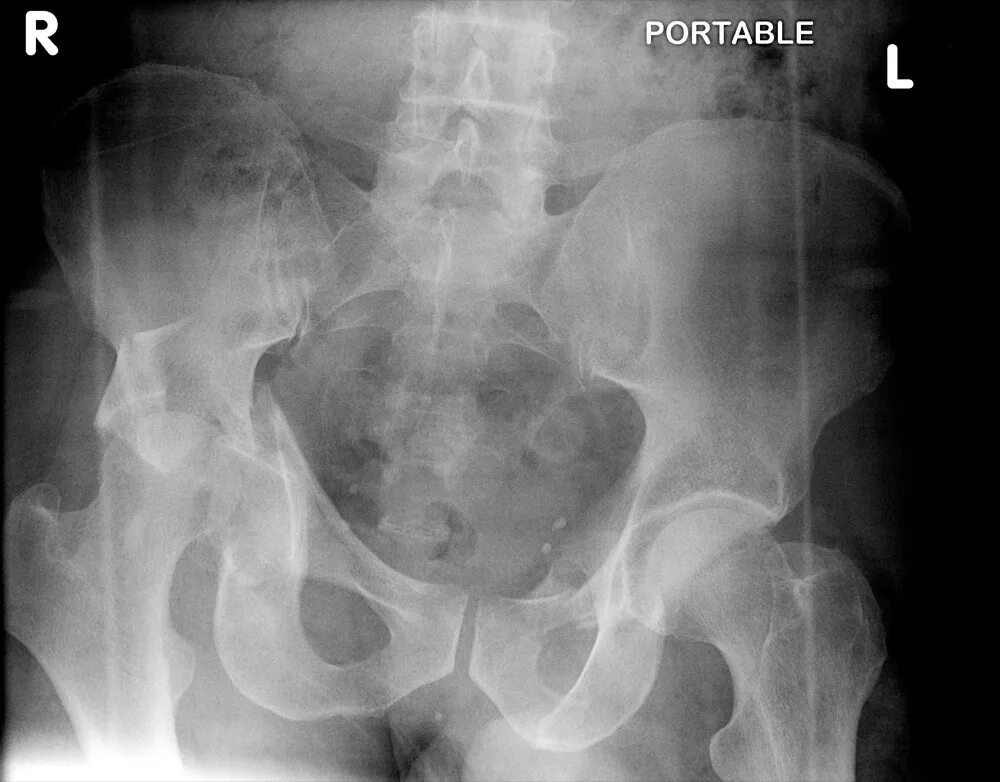

Рентген тазобедренный в двух проекциях